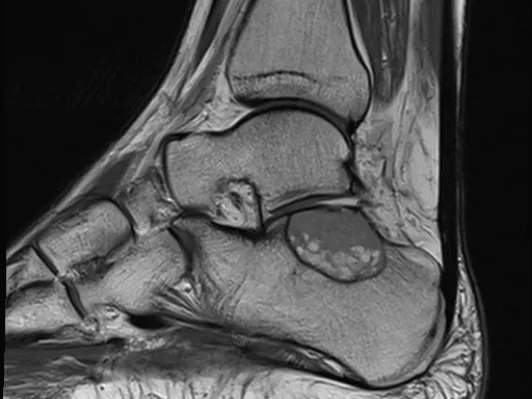

Musculoskeletal Imaging – Ankle MRI Fellowship

This MSK MRI course will cover the entire ankle joint and its surroundings, including joint surfaces, bones, ligaments, and tendons. It will in-depth explain how to understand and how to report MRI studies of the ankle, emphasizing common and uncommon complaints and findings. Injuries, degeneration, stress changes, and normal anatomic variants will be covered – enabling the attendees to report ankle studies with confidence. This is a comprehensive MRI course, with lectures and case sessions, in a smaller group with close interactions with an experienced lecturer and MSK radiologist.